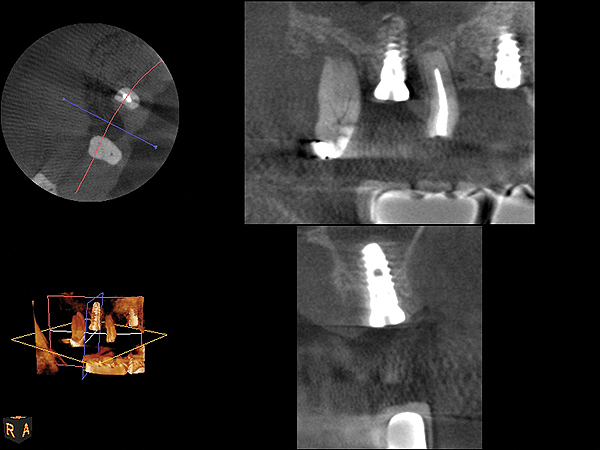

Fig 7. 4-month CBCT scan (Kodak 9000D) of implant No. 14.

Figure 7

Fig 12. CBCT scan (Kodak 9000D) showing 3.5-month postoperative of implant No. 3 in place. Note homogenous appearance of the bone.

Figure 12

Fig 19. CBCT scan (Kodak 9000D) of implant No. 14 showing homogeneous appearance of the bone.

Figure 19

Fig 22. CBCT scan (Kodak 9000D) of No. 3 area, day of placement. Appearance of native bone and bone graft is clearly discernible.

Figure 22